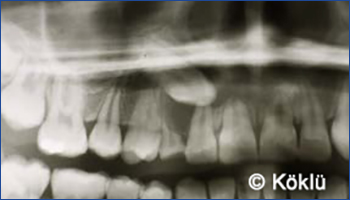

Patienten Beispiel "Überzahl von Zähnen im Oberkiefer"

Patienten Beispiel "Verlagerter Zahn im Oberkiefer"

Zähne, die im Kiefer angelegt sind, jedoch aufgrund einer Verlagerung nicht normal durchbrechen können, tragen ebenfalls zu Zahnfehlstellungen bei und können ohne Extraktion eingeordnet werden.